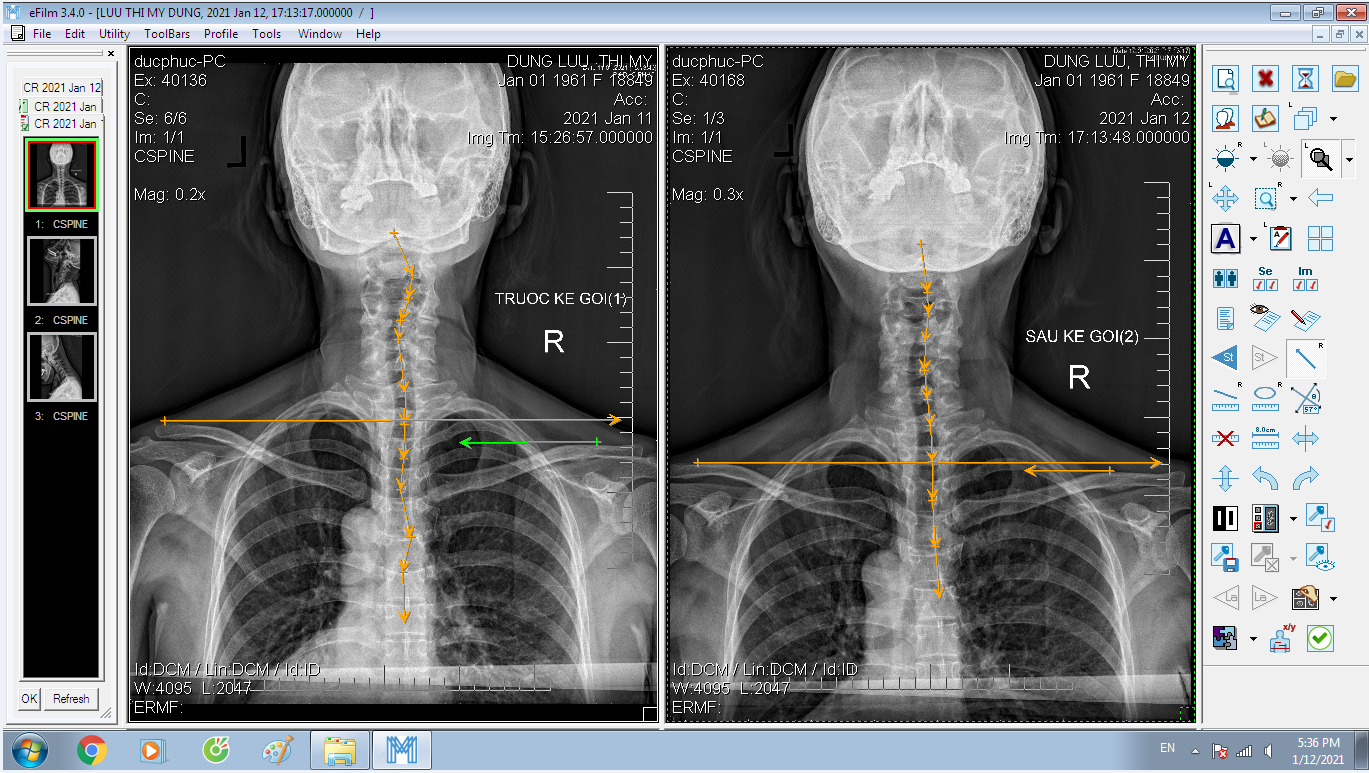

DOCTORLOAN đã thành công trong điều chỉnh xương khớp về đúng vị trí trong thời gian ngắn